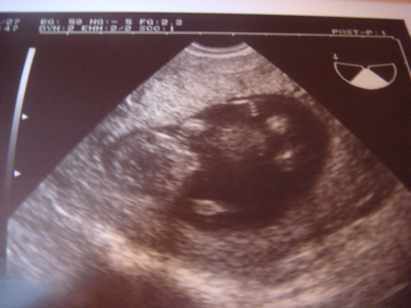

Pocimaci CRL 59,4mm hosszú, BPD 21mm, combcsont 9mm :lol: és a lényeg: NT 1,1mm.

Szóval minden a legnagyobb rendben. Méretei szerint akár egy héttel idősebb is lehet. Luca 12+6naposan volt CRL 60mm.

Megint riszált, szóval ajánlom, hogy lány legyen! :lol:

Jól átbogarásztuk a gerincét, kezeit, lábait. Tetőtől talpig megkukkoltuk!

Na a képek (a második babafotól látjátok, hogy összeüti az apró lábait. Kb fél cm lehet, vagy annyi sem egy tappancs):